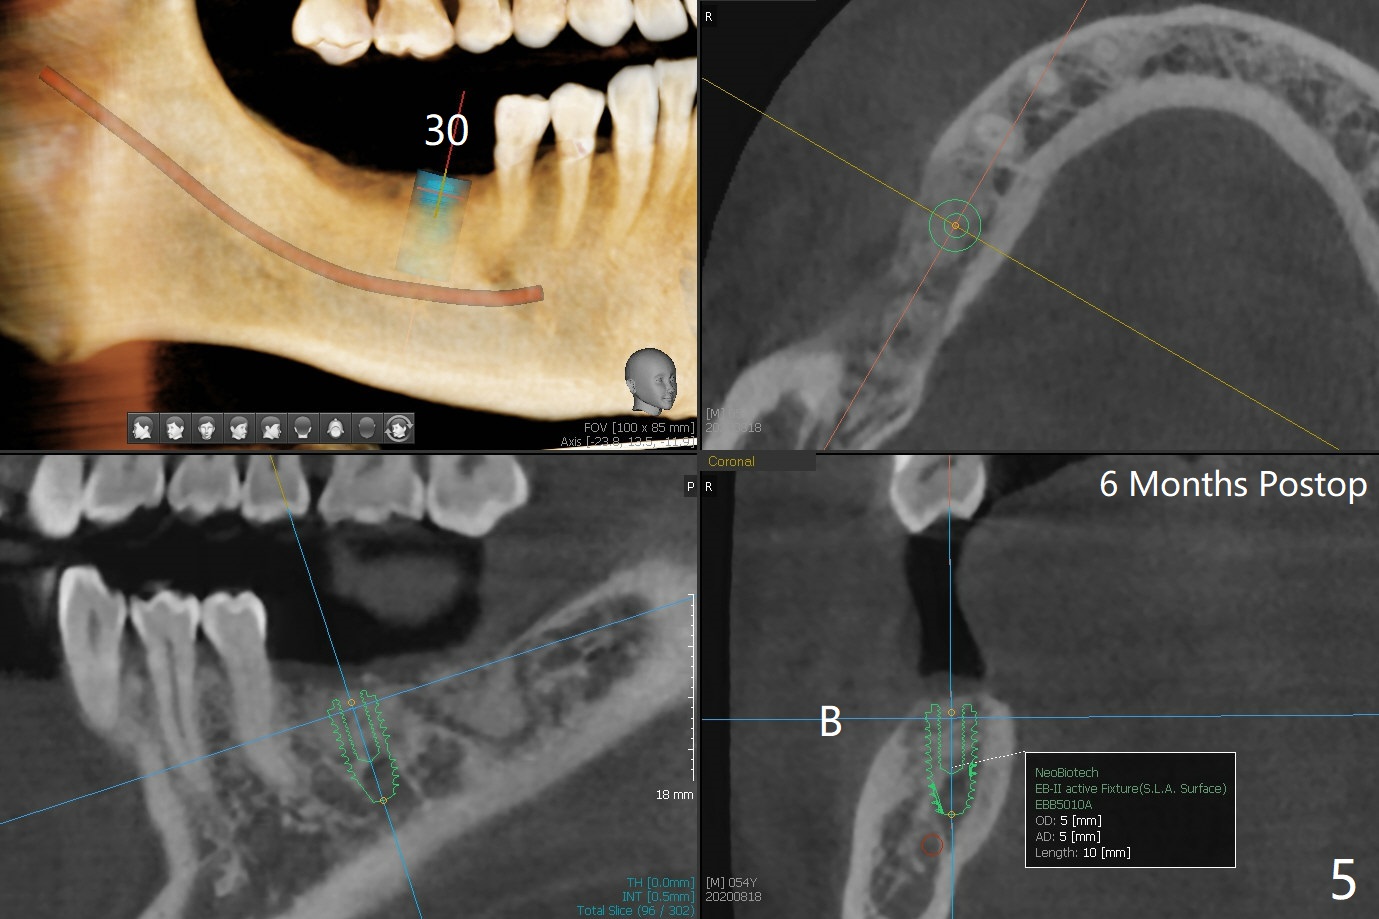

A 53-year-old man requests extraction of #30 and 31 post-SRP (Fig.1 (*: furca radiolucency). There is severe hemorrhage from the sockets post extraction, which makes bone graft difficult (Fig.2). Osteogen plug should have been used in stead of Ossogen. The socket openings are closed with 12x12 and 8x8 mm BioXclude and 4-0 PGA. The root curvature of the tooth #29 (Fig.2 *) suggests bruxism. The sockets heal 12 days postop (Fig.3). The septum at #30 (Fig.1 *) remains 6 months postop. Be wary of deviation off the septum during osteotomy. Bone density at #30 and 31 is high (1400-1700 units, Fig.5,6). Be careful of bone heat during osteotomy. It appears that cortical taps are pending.